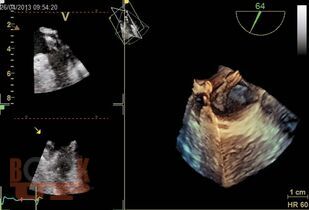

Книга посвящена методу чреспищеводной эхокардиографии, в основном многоплановой чреспищеводной эхокардиографии, которая в настоящее время является наиболее распространенным вариантом чреспищеводного исследования. Уделено внимание вопросам безопасного использования этого высокоинформативного метода. Подробно анализируются возможные осложнения и меры предосторожности при выполнении исследования. Приведены основные доступы и позиции при многоплановой чреспищеводной эхокардиографии и способы их выведения, терминология доступов и позиций, а также манипуляций датчиком. Основные ультразвуковые позиции сопоставлены с топографическими сечениями на анатомической модели чреспищеводного симулятора. Описаны сердечные структуры в норме и при различных патологических состояниях. Представлены возможности и ограничения метода, его клиническое значение.